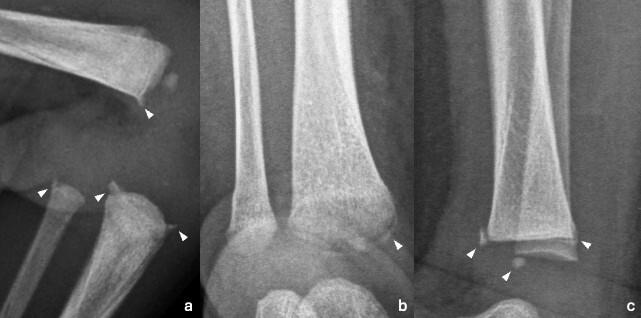

Les fumeurs dont les résultats du scanner baseline de dépistage étaient normaux présenteraient un risque de cancer du poumon nettement accru à long terme, qui n'est devenu significatif qu'au bout de deux ans après le dépistage (

étude).